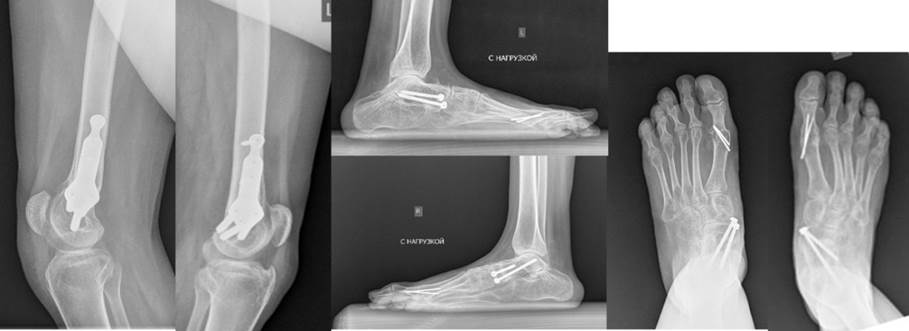

Hirurgija za korekciju šeme hoda (crouch gait) kod cerebralne paralize

CROUCH GAIT („hodanje na polusavijenim kolenima“)

Karakteriše fleksija kolena veća od 15° u vreme inicijalnog kontakt faze oslonca ciklusa koraka, kao i trajni položaj stopala u položaju dorsifleksije, fleksija kuka, koja se često kombinuje sa intratorzionim deformitetom butne kosti, spoljašnja rotacija stopala u odnosu na vektor kretanja pacijenta zbog teškog plano-valgusa deformiteta stopala sa izuzetno izraženom abdukcijom prednjeg dela i/ili spoljnog torzionog deformiteta kostiju potkolenice, karlica može biti u normalnom položaju ili nagnuta unazad

Klinički slučaj

Pre operacije:

• Sporo hodanje sa šetačem

• Fleksijske kontrakture kolena

• Visoki položaji kolena

• Deformiteti stopala

Hirurški izvedeno:

• Ekstenzija nogu postignuta

• Spuštanje patele

• Produženje mišića odgovornih za kontrakture

• Otklanjanje deformiteta stopala

1,5 godine nakon operacije:

• Brzo samostalno hodanje

• Nema potrebe za šetačima

• Dobri uslovi za dalju rehabilitaciju

Pre lečenja

Nakon lečenja